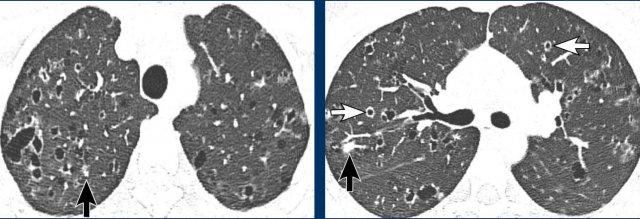

Các nang trong BHD có xu hướng phân bố ưu thế ở vùng phổi thấp và ngoại vi.

Đôi khi các nang có ranh giới được xác định bởi các vách liên tiểu thùy, tạo cho chúng hình dạng tam giác hoặc thấu kính đặc trưng (đầu mũi tên trong hình 2 và 4).

Các nang BHD không nhiều, thường ít hơn 50 nang. Đôi khi số lượng nang rất ít với hình ảnh rất tinh tế (hình 3), nhưng không được bỏ sót.

Hình ảnh

- Các nang BHD. Một số nang tiếp giáp với màng phổi (mũi tên vàng) hoặc các rãnh liên thùy. Các nang ở vùng phổi thấp cũng có thể gặp trong LIP. Khí phế thũng cạnh vách liên tiểu thùy có phân bố ưu thế ở vùng phổi trên.

- Phân bố ưu thế ở vùng phổi thấp và các nang hình tam giác (đầu mũi tên) trong BHD.

- Lưu ý hình ảnh rất tinh tế với phân bố ưu thế ở vùng phổi thấp.

- Các nang BHD điển hình

Đây là hình ảnh của một phụ nữ 56 tuổi, có tiền sử tràn khí màng phổi tái phát và hiện tại nhập viện lần này cũng vì tràn khí màng phổi (mũi tên).

Nhận xét hình ảnh

Có nhiều nang thành mỏng – hơn bốn nang. Lưu ý vị trí phân bố gần các rãnh liên thùy và ở ngoại vi phổi.

Kết luận

Đây là trường hợp hội chứng Birt-Hogg-Dubé (BHD).

Hai bệnh phổi dạng nang thường biểu hiện bằng tràn khí màng phổi là LAM và BHD.

LAM biểu hiện là các nang đơn thuần, thành mỏng, hình tròn hoặc bầu dục, đều đặn với phân bố lan tỏa.

Vị trí ngoại vi và cạnh rãnh liên thùy của các nang BHD thường tạo ra các góc nhọn, khiến chúng có hình dạng thấu kính.

Khi các nang có hình ảnh đặc trưng này, chúng có độ đặc hiệu cực kỳ cao cho chẩn đoán hội chứng Birt-Hogg-Dubé.

Đây là một trường hợp khác của hội chứng Birt-Hogg-Dubé.

Các nang có vị trí điển hình ở ngoại vi phổi gần trung thất (mũi tên đen) và gần rãnh liên thùy (mũi tên trắng).

Đây là một trường hợp minh họa khác với rất ít nang nhỏ ở bệnh nhân mắc hội chứng Birt-Hogg-Dubé.

Đôi khi cần phải quan sát rất kỹ các trường phổi để không bỏ sót các nang và bỏ lỡ chẩn đoán BHD.

Trong trường hợp này, có thể hình dung rằng nếu CT được thực hiện vì lý do khác, người đọc có thể dễ dàng bỏ sót những nang nhỏ này.

Cần nhớ rằng khi phát hiện hơn bốn nang và chúng thực sự là nang, cần phải xử lý các phát hiện này.